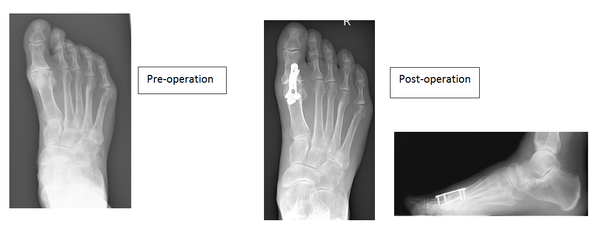

Joint fusion (Arthrodesis)

This operation is generally considered to be the gold standard and is definitive with regard to alleviating pain at the expense of all joint movement.

This is offset by fusing the great toe in slight elevation allowing you to rock through the toe, studies have shown improved weight bearing through the foot following this procedure.

It involves removing both surfaces of the joint and aligning the big toe to allow comfortable walking. The new position is maintained with screws and plates allowing the two bones to join together.

The fixation rarely troubles patients but the plate and screws can be removed if required. The main risk with this procedure is a non-union and the literature suggests around a 6% chance of it happening.